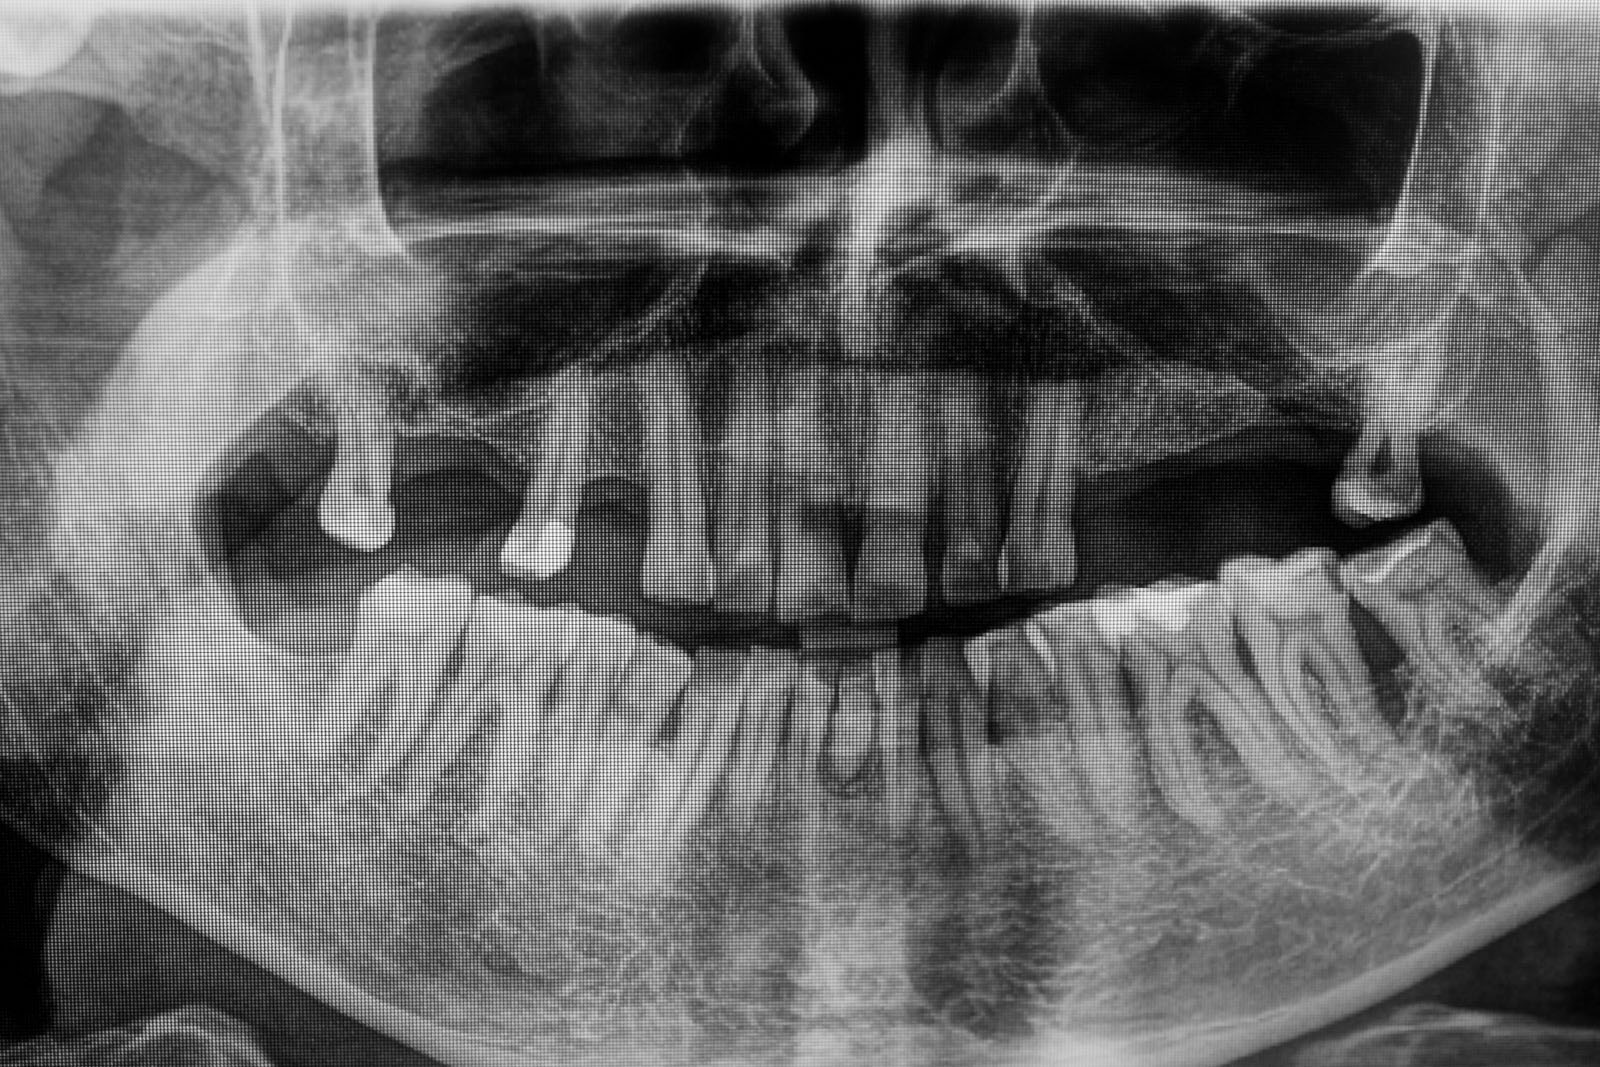

Przed podjęciem leczenia należy określić stopień zaniku kości szczęk oraz żuchwy. W tym celu przeprowadza się badanie kliniczne oraz odpowiednią diagnostykę obrazową pacjenta. Uwzględnia ona zdjęcie panoramiczne OPG jako podstawę dwuwymiarowego obrazowania podłoża kostnego oraz możliwe jest badanie tomograficzne CT lub bardziej precyzyjna tomografia stożkowa CBCT. Opcjonalnie wykorzystywana diagnostycznie tomografia pozwala na bardziej wnikliwą ocenę stopnia zaniku kości w trójwymiarowym, przestrzennym obrazie.